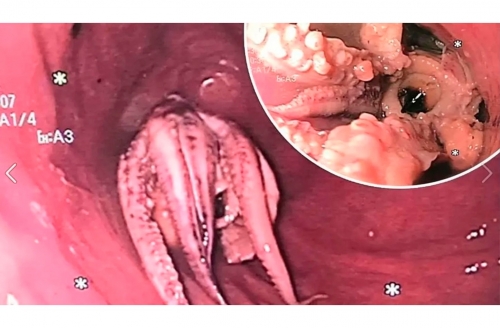

The American Gastroenterological Association (AGA) shared images taken showing the eight-tentacled creature stuck in the man's oesophagus.

Doctors there conducted a quick CT scan, which revealed a super-dense mass in the man's oesophagus, but they couldn't be sure what it was without an esophagoscopy, which involves inserting a small, flexible tube with a camera at the end, and discovering that the man had a whole octopus stuck in his stomach.

At first, the doctors tried the "push technique," but it soon became clear that the octopus would not go down and excessive pressure would rupture the oesophagus.

So they had to use forceps to grab the sea creature and pull it out.